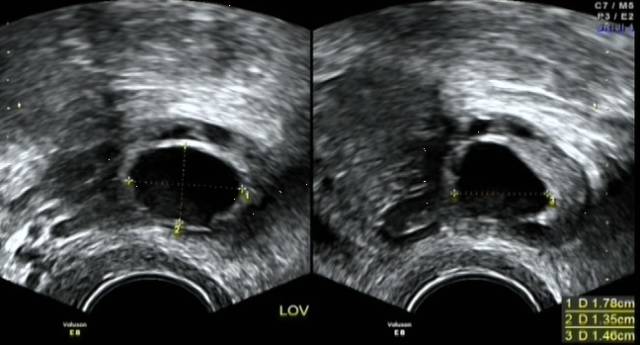

卵巢皮质内由一个卵母细胞和其周围许多小型卵泡细胞所组成。根据卵泡发育过程的形态和功能变化,可分为原始卵泡、生长卵泡和成熟卵泡三个阶段。每一月经周期中只有一个卵泡生成至成熟,叫做优势卵泡。其它卵泡受抑制因子的抑制,停止生长,退化为闭锁卵泡。成熟的优势卵泡迅速长大,直径达20mm,并逐渐移行至卵巢表面,准备排卵。